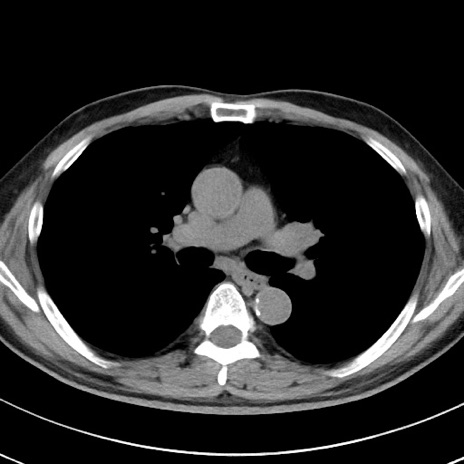

【腹部TIPS】症例29 参考症例 CT(横断像)

症例

70歳代男性